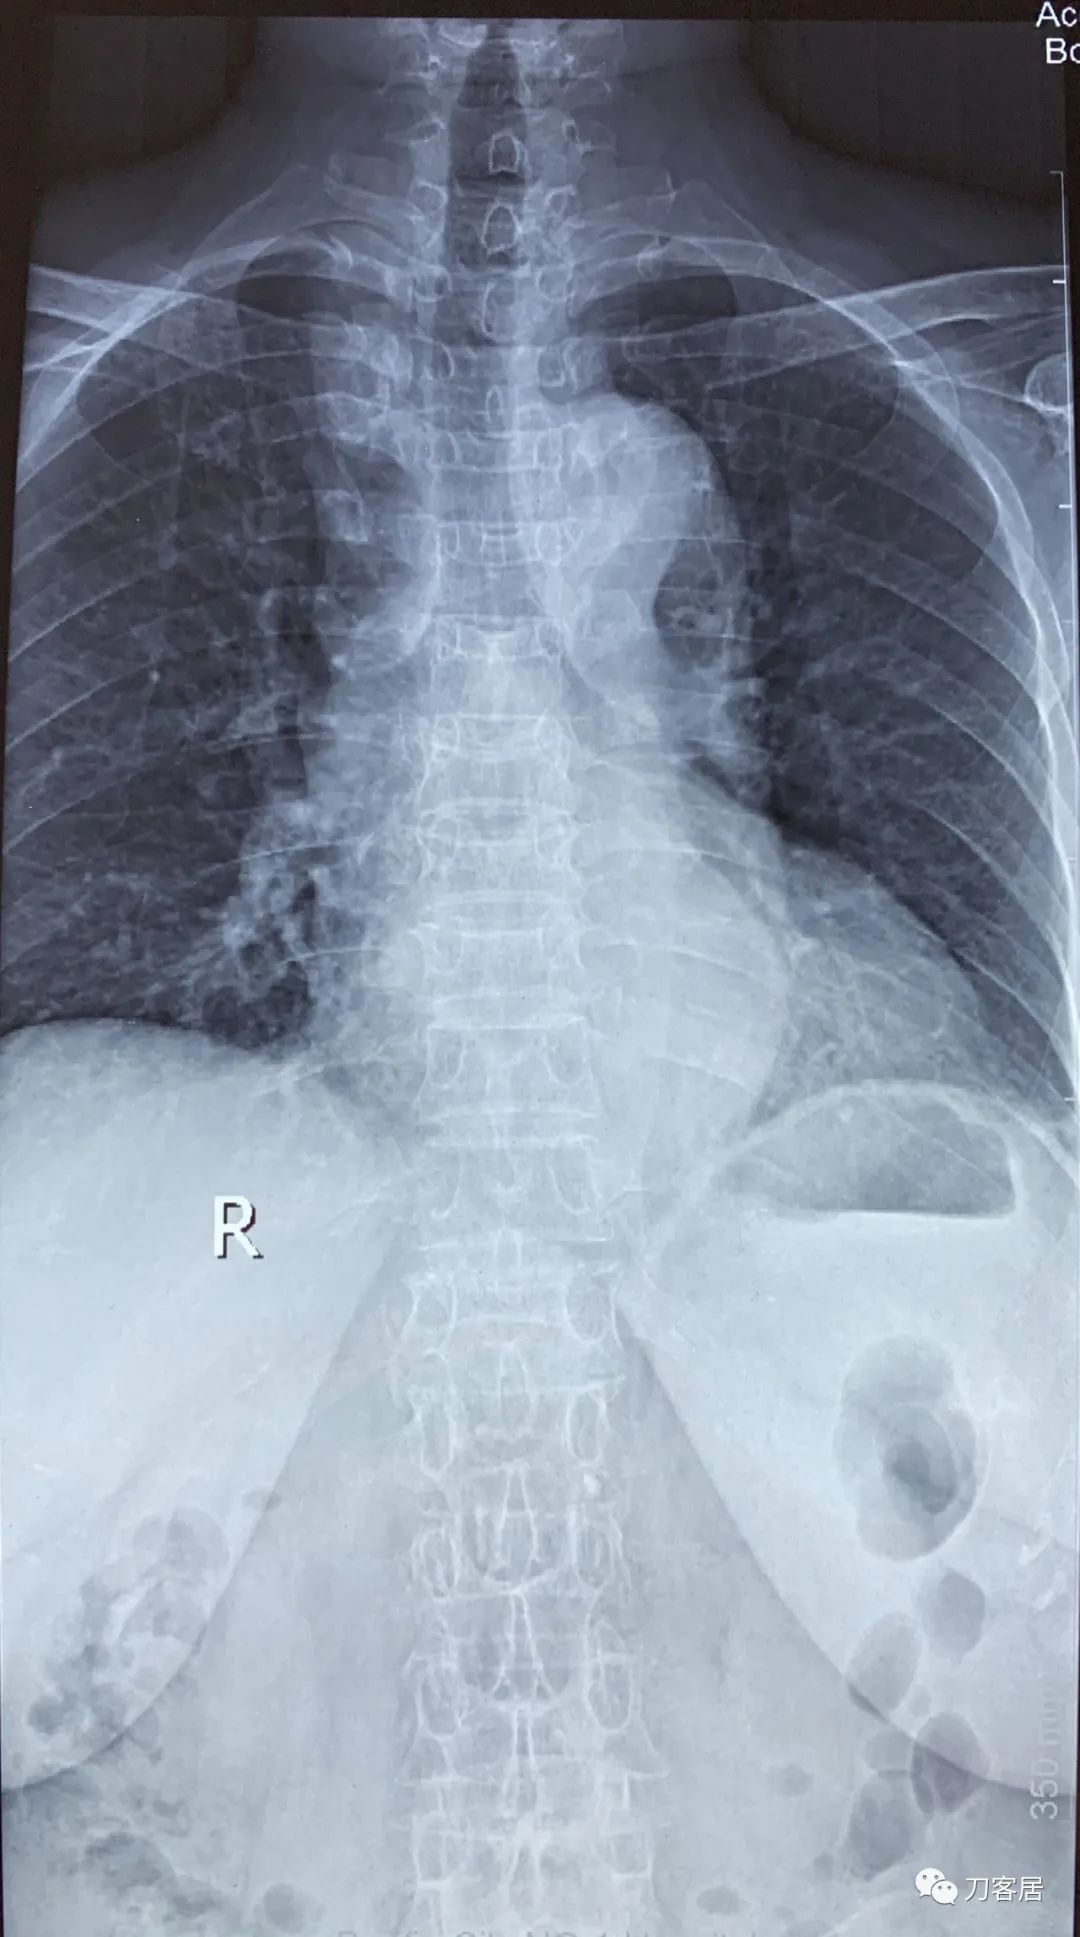

自带影像学资料提示胸椎,腰椎多发脊柱压缩性骨折。

诊断 : 重度骨质疏松症,胸椎、腰椎多发椎体压缩性骨折

图01-20200825胸椎正位X线片

图02-20200825胸椎侧位X线片